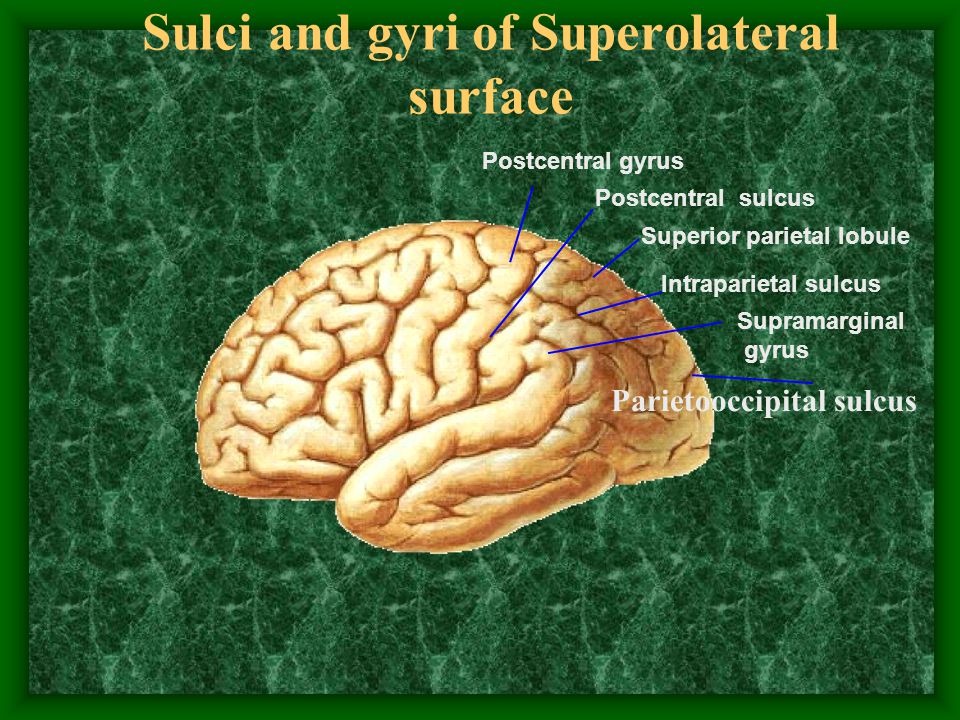

Супрамаргинальная извилина: Функции и Исследования